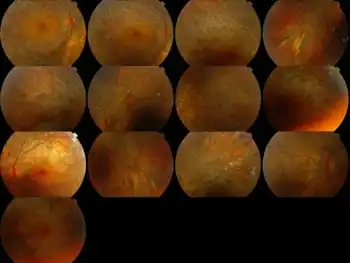

Bietti's crystalline dystrophy (BCD) is a rare autosomal recessive[2] eye disease named after G. B. Bietti.[3]

Symptoms of BCD include:

- Crystals in the cornea (the clear covering of the eye)

- Yellow, shiny deposits on the retina

- Progressive atrophy of the retina, choriocapillaries and choroid (the back layers of the eye). This tends to lead to progressive night blindness and visual field constriction.

In terms of the diagnosis we find that it is based on the clinical findings of typical crystalline deposits (cornea and retina)[8]